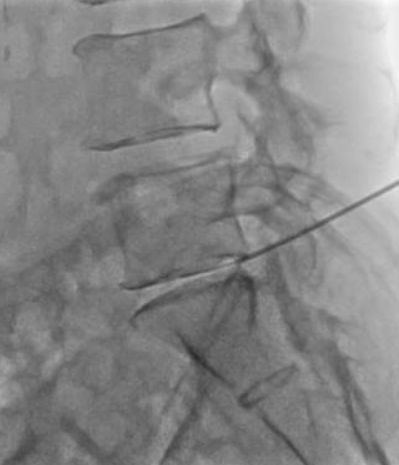

治療について

患者様と相談の元、L5/sにPODDを施行

治療は末松医師が行いました。

針を椎間板に刺入後オゾンを入れて治療終了となります。

治療は10分程度で終了

回復室で休憩後、歩いて帰院されました。